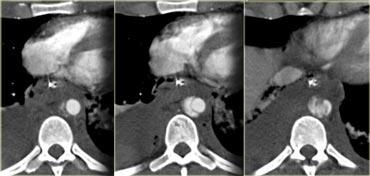

Dấu hiệu thoát thuốc cản quang (Contrast blush)

Dấu hiệu thoát thuốc cản quang được định nghĩa là vùng tăng tỷ trọng với giá trị đo trong khoảng mười đơn vị Hounsfield (HU) so với mạch máu lân cận (hoặc động mạch chủ).

Chẩn đoán phân biệt bao gồm:

- Thoát thuốc cản quang động mạch hoạt động

- Giả phình mạch sau chấn thương

- Rò động-tĩnh mạch sau chấn thương

Làm thế nào để phân biệt các thực thể này?

- Dấu hiệu thoát thuốc cản quang vượt ra ngoài ranh giới của tạng thì chắc chắn là thoát thuốc ngoài mạch.

- Trong giả phình mạch hoặc rò động-tĩnh mạch, thuốc cản quang sẽ được rửa trôi theo dòng máu.

- Nếu có thoát thuốc cản quang động mạch hoạt động và chụp thì muộn, thuốc cản quang sẽ không bị rửa trôi.